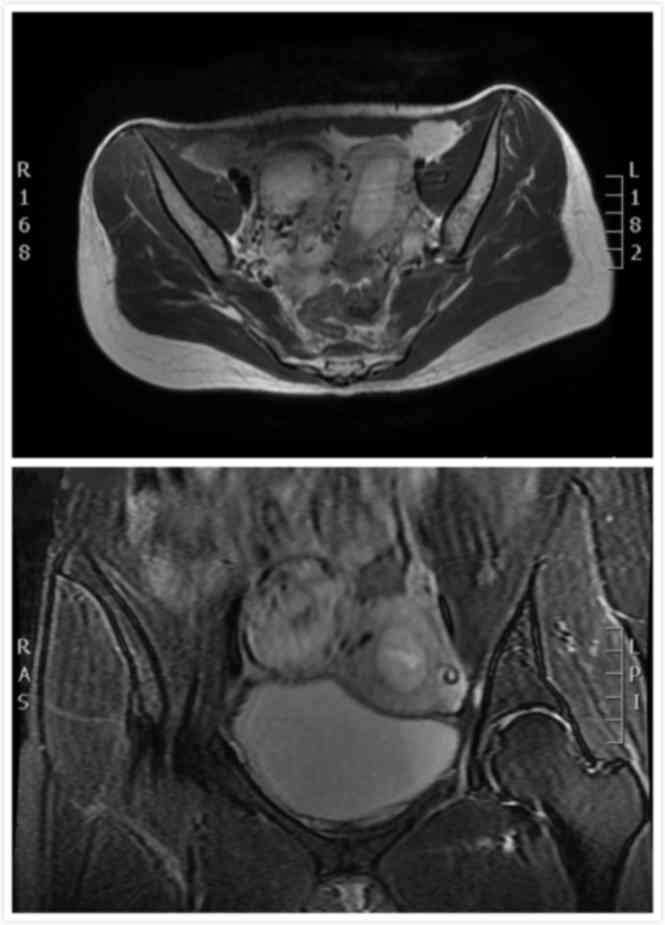

ultrasound and the pelvic magnetic resonance imaging (MRI) scan are

Pelvic MRI shows the endometrial thickening and gestational

trophoblastic disease in the rudimentary uterine horn. The chest

X-ray was negative.